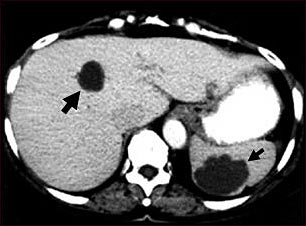

Esta TC abdominal muestra múltiples quistes en el hígado y el bazo. Se puede ver un quiste circular oscuro en el hígado (lado izquierdo de la pantalla) y un gran quiste circular irregular en el bazo (parte inferior derecha de la pantalla).